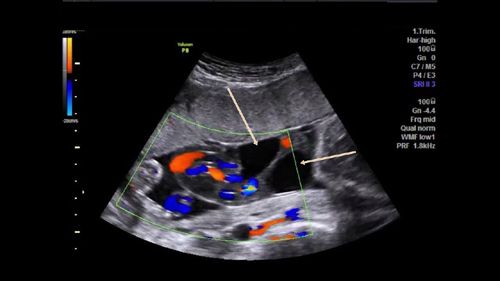

Challenge your diagnostic skills with these images from a young woman with right pelvic pain and a history of amenorrhea.